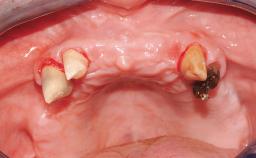

Rehabilitating an Edentulous Maxilla with a Fixed Dental Prosthesis Following Provisional Immediate Loading

This case features the flapless computer-guided placement of 7 bone-level implants, distributed to provide maximal support for the prosthetic framework. A rigid one-piece metallic framework was utilized as an interim restoration to reduce the risk of fracture associated with this prosthetic design. As part of the clinical examination, the SAC Assessment Tool was used, resulting in a surgical and restorative risk classification as “complex”.

Case Type Edentulous Maxilla

Jaw Maxilla

Area Full-Arch